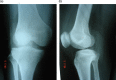

(A and B) Anteroposterior and lateral X-rays of the right knee showing posterolateral subluxation.